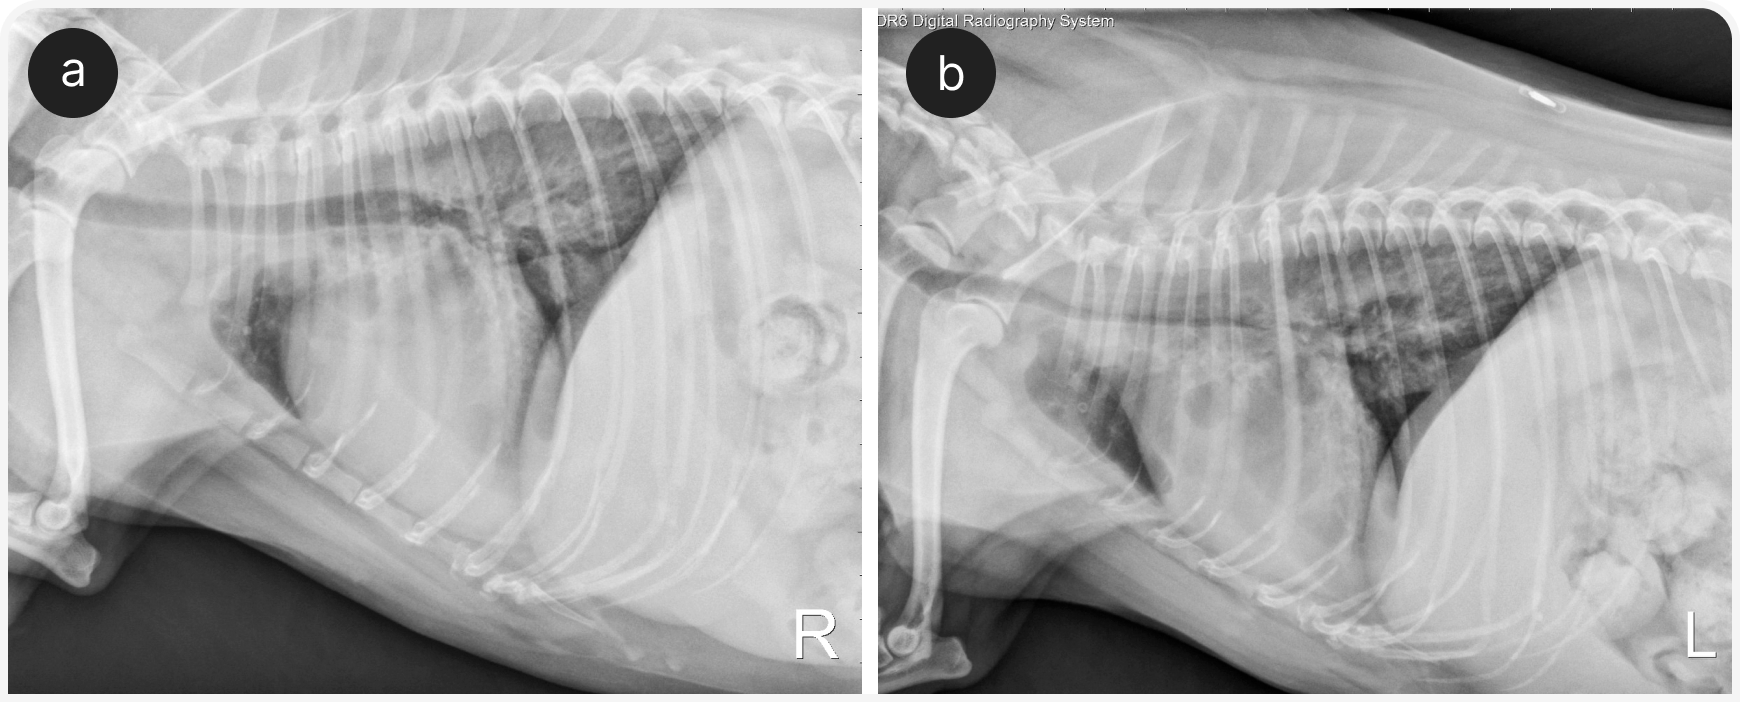

Диагностика коллапса дыхательных путей по рентгенограммам шейного отдела и грудной клетки ненадежна (8), но иногда позволяет выявить сопутствующие легочные заболевания, например пневмонию или бронхоэктазы, и заболевания сердца. Если сделать рентгенограммы в боковой проекции и на вдохе, и на выдохе, можно лучше визуализировать изменение просвета дыхательных путей: на полном вдохе можно обнаружить коллапс шейной части трахеи, а на выдохе — уменьшение размеров просвета внутригрудной части трахеи или крупных бронхов (Рисунок 1).

В целом при рентгенографии часто получают ложноположительные результаты, в то же время степень коллапса часто остается недооцененной, место коллапса удается определить не всегда, а документирование внутригрудного коллапса дыхательных путей или долевого бронхиального коллапса ненадежное.